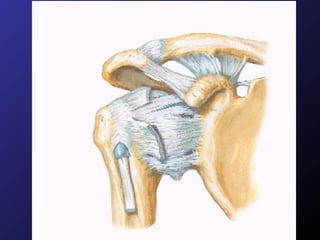

Factores estructurales Tres factores que previenen movimientos anormales. Contornos recíprocos Cápsula articular y ligamentos Músculos

Lesiones Asociadas Cápsula fibrosa. Lux. Intracapsular Cápsula y periostio son distendidos por traumatismo, no se atraviesan por hueso lesionado. Lux. Extracapsular Cápsula y periostio son distendidos y atravesados por algún extremo óseo. En ojal Extremo óseo grande queda atrapado en cápsula y extremo pequeño atraviesa cápsula. EG    Cadera.

Lesiones Asociadas Cápsulafibrosa. Lux. Intracapsular Cápsula y periostio son distendidos por traumatismo, no se atraviesan por hueso lesionado. Lux. Extracapsular Cápsula y periostio son distendidos y atravesados por algún extremo óseo. En ojal Extremo óseo grande queda atrapado en cápsula y extremo pequeño atraviesa cápsula. EG  Cadera.